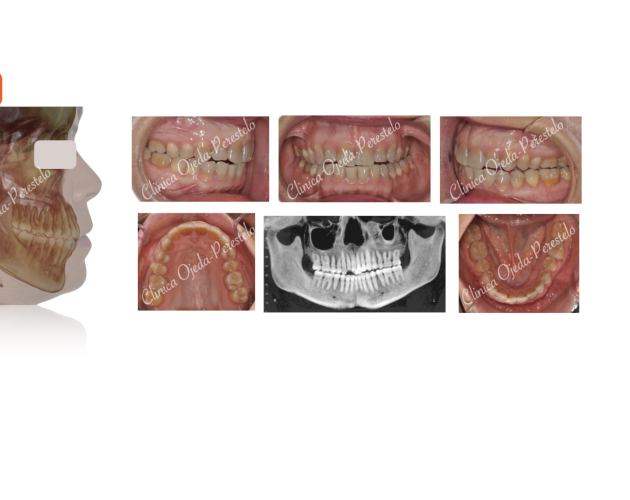

Mordida Abierta de molar a molar Casos de Éxito - Adultos

Clase II esquelética con Cirugía de Avance Md Casos de Éxito - Ortodoncia Plástica (Invisalign/Angel) - Adultos

Asimetría Facial en Clase III ósea y C.Ortognática Casos de Éxito - Mordida Cruzada - Adultos - Cirugía Ortognática

Clase III esquelética en dentición temporal Casos de Éxito - Niños

Clase II esquelética en niño con apnea moderada Casos de Éxito - Niños

Caso Ortodoncia Lingual Superior con Vestibular Inferior Casos de Éxito - Ortodoncia Lingual

Caso Multidisciplinar: Ortodoncia- Coronas sobre Implantes Casos de Éxito - Adultos - Casos Multidisciplinares

Caso Multidisciplinar: Ortodoncia-Implantes-Pónticos-Bioestética Casos de Éxito - Adultos - Casos Multidisciplinares

2ºMolar Mandibular Retenido Casos de Éxito - Dientes Retenidos

Caso Multidisciplinar: Ortodoncia-Implantes-Bioestética 11-21 Casos de Éxito - Casos Multidisciplinares

Caninos Maxilares Retenidos (13-23) + Bioestética 21-22 Casos de Éxito - Niños - Dientes Retenidos - Casos Multidisciplinares

Premolar Mandibular Retenido (35) Casos de Éxito - Niños - Dientes Retenidos

Clase II con Mordida Abierta Casos de Éxito - Ortodoncia Plástica (Invisalign/Angel) - Adultos

Clase II severa en Mandíbula Hipoplásica Casos de Éxito - Adultos - Cirugía Ortognática

Expansión Maxilar Asistida en Mord.Cruzada Casos de Éxito - Mordida Cruzada - Adultos - Cirugía Ortognática

Mordida Cruzada Unilateral con Apiñamiento Severo Casos de Éxito - Mordida Cruzada - Adultos

Mordida Cruzada Bilateral Casos de Éxito - Mordida Cruzada - Niños

Clase III esquelética en dentición definitiva Casos de Éxito - Niños

Mordida Cruzada con dolor Craneofacial Casos de Éxito - Ortodoncia Plástica (Invisalign/Angel) - Mordida Cruzada - Adultos

Clase III ósea severa con C.Ortognática Casos de Éxito - Mordida Cruzada - Adultos - Cirugía Ortognática

Asimetría Facial en Clase III ósea y C.Ortognática Casos de Éxito - Mordida Cruzada - Adultos - Cirugía Ortognática - Casos Multidisciplinares

Biprotusión esquelética con Sonrisa Gingival Casos de Éxito - Adultos - Cirugía Ortognática

Clase II osea de causa Md con Cara Larga Casos de Éxito - Adultos - Cirugía Ortognática

Clase II ósea con Resalte muy Aumentado y Extracciones dentarias Casos de Éxito - Adultos - Casos Multidisciplinares

Apiñamiento severo con molares con mal pronóstico Casos de Éxito - Adultos

Mordida Abierta Posterior con M. Cruzada en clase III ósea Casos de Éxito - Mordida Cruzada - Adultos

Clase III ósea tratada con Exo de cordales y Microtornillos Casos de Éxito - Mordida Cruzada - Adultos

Clase II con apiñamiento y sobremordida severa Casos de Éxito - Ortodoncia Plástica (Invisalign/Angel) - Adultos

Sonrisa gingival (encías) con Resalte Aumentado Casos de Éxito - Mordida Cruzada - Adultos

Clase III esquelética en dentición mixta Casos de Éxito - Niños

Canino Mandibular Retenido (33) Casos de Éxito - Dientes Retenidos

Mordida Cruzada y Abierta severa Casos de Éxito - Mordida Cruzada - Adultos

Ortodoncia-Implantes-Bioestética 22 Casos de Éxito - Ortodoncia Plástica (Invisalign/Angel) - Adultos - Casos Multidisciplinares

C Multidisciplinar: Orto Plástica + MASPE+ Corticotomías + Regen Casos de Éxito - Ortodoncia Plástica (Invisalign/Angel) - Mordida Cruzada - Adultos - Cirugía Ortognática - Casos Multidisciplinares

Mordida invertida en clase III (MARPE +Orto Plástica + elásticos Casos de Éxito - Ortodoncia Plástica (Invisalign/Angel) - Mordida Cruzada - Adultos